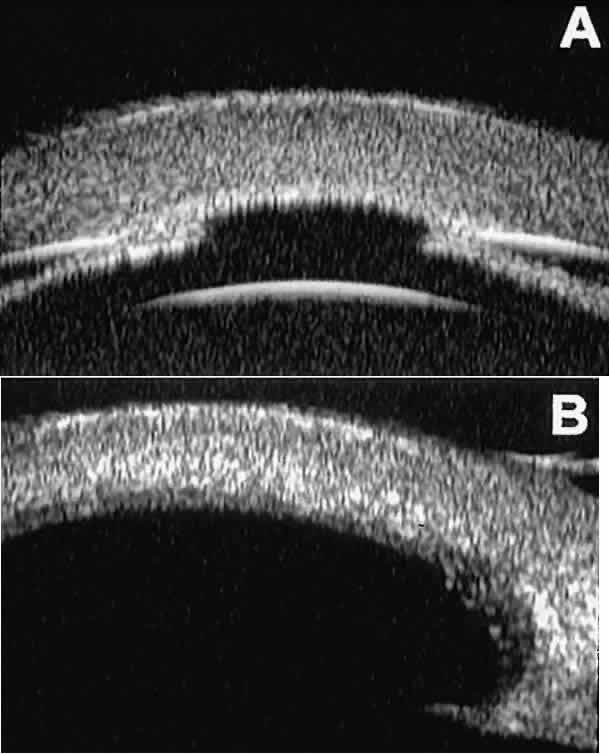

The role of UBM in the preoperative assessment of eyes with cataract is as yet unknown. In certain eyes, however, UBM may reveal features or abnormalities that could alter the ophthalmologist's surgical approach. Postoperatively, UBM can show the size and location of an intraocular lens (IOL) and the positioning of the haptics. A posterior chamber IOL appears on UBM as a highly reflective plate (corresponding to the lens optic) in the retropupillary plane with reverberation artifacts behind it (Fig. 17A). In contrast, an anterior chamber IOL appears on UBM as a sonoreflective plate located anterior to the pupillary plane (see Fig. 17B). In most eyes with a posterior chamber IOL, UBM can show whether the haptics are in the capsular bag (Fig. 18A), in the ciliary sulcus (see Fig. 18B), or in some other anatomic location12 (e.g., resting on the peripheral iris or secured with sutures to the sclera). The haptics are easier to locate if they are made of polymethyl-methacrylate than if they are made of proline because the former has a stronger reflectance.

Fig. 17. Composite UBM images of intraocular lenses. A. Posterior chamber IOL. B. Anterior chamber IOL.

Fig. 18 . Localization of posterior chamber IOL haptics by UBM. A. Haptic in capsular bag (arrow). B. Haptic (bright object just behind peripheral iris) in iridociliary sulcus.